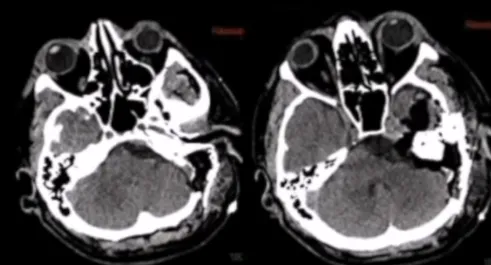

Labbé静脉呈现出规则的解剖形态,术前CT扫描有助于评估骨骼解剖,包括肿瘤的钙化、岩尖的气化以及乙状窦后空间。同样重要的是评估中颅窝底在膝状神经节上方可能存在的裂开,以及在颈动脉管水平可能存在的裂开,以减少在手术入路过程中对这些结构的损伤风险。此外,福教授还评估了颈静脉球的高度与内听道的关系。

术前血管造影可以评估肿瘤的血供。这个序列显示了来自咽升动脉的血供,以及来自颈内动脉的硬脑膜支,由下外侧干和脑膜垂体干表示。通过在咽升动脉处放置线圈进行栓塞,手术前一天进行,可以显著减少术中出血。

术后CT未显示任何术后并发症,术后MRI显示脑膜瘤几乎完全切除。